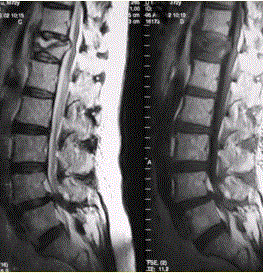

问题 患者男,70岁,因肝癌入院,准备行肝移植手术。住院期间因腰扭伤而腰痛,故行腰椎MRI检查(如下图)。 正确的诊断为

选项 A.肝癌椎体转移 B.椎体骨质疏松性压缩性骨折 C.单发椎体浆细胞瘤 D.单发椎体结核 E.椎体嗜酸性肉芽肿 F.Paget病

答案 B